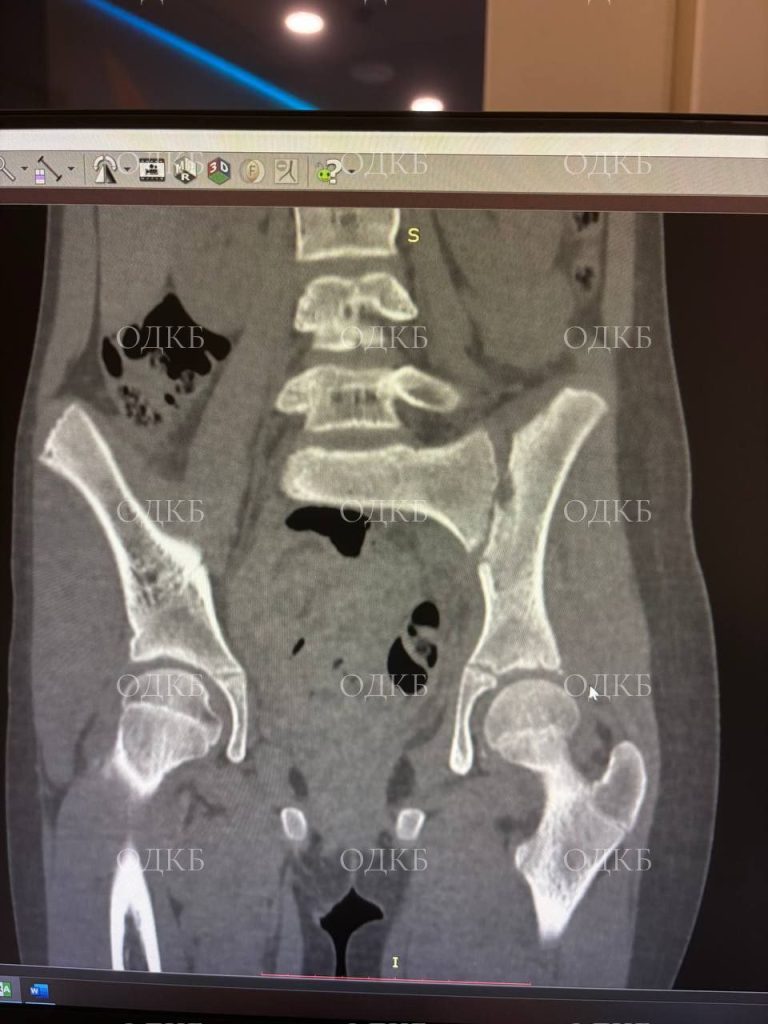

Специалисты провели полное обследование ребёнка: сделали КТ, МРТ, УЗИ, забрали анализы. Симптомы долго не позволяли чётко определить, какой орган тела девочки поражён. Симптомы очень схожи с клиникой «острого живота», артритом, радикулитом и почечной коликой. Ребёнок находился в вынужденном положении, активные движения в ногах были ограничены из-за сильных болей.

Необходимо было быстро принять верные решения, чтобы помочь девочке. Рентгенологи и врачи УЗИ увидели признаки сакроилеита, очаг поражения и деструктивные изменения в крестцово-подвздошном суставе. Определить, был ли это гнойный процесс или клиника артрита, врачи смогли только во время операции.

Очаг поражения был расположен глубоко внутри таза. Специалисты выявили абсцесс в проекции КПС. Если бы врачи вовремя не установили правильный диагноз и не устранили гной, он мог распространиться в брюшной полости, спинно-мозговом канале, и тазобедренном суставе. Это привело бы к более тяжёлым заболеваниям, и девочка была бы прикована к инвалидному креслу.